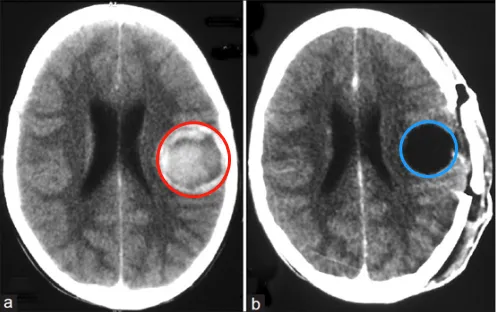

快!患者意识模煳,右侧肢体瘫痪! 凌晨3点,45岁的Laura被推入急救室,因突发脑干海绵状血管瘤出血,导致她面瘫、偏瘫,当她被送到医院时,情况已经十分糟糕。她能平安度过这一劫吗?...